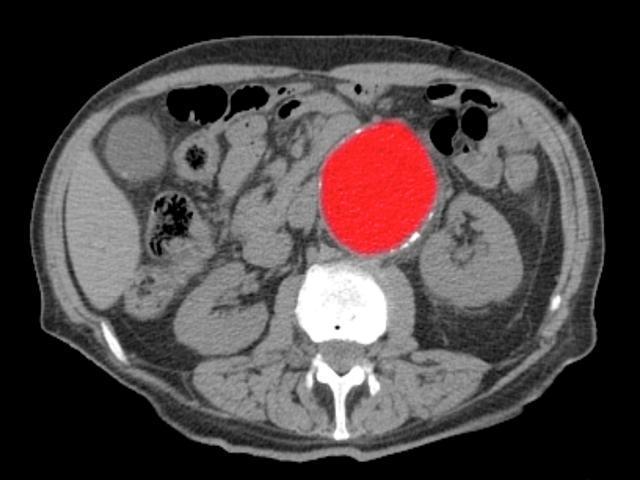

Aort diseksiyonu yani ana atardamarda yırtılmanın, kalp cerrahisinin karşılaştığı en acil durumlardan biri olduğunu belirten Prof. Dr. Köksal, bu hastaların fakat yarısının hastaneye ulaşabildiğini, ameliyat olanların ise sırf yarısının hayatta kalabildiğini tabir etti.

“Bu yırtıkların temelinde çoklukla aortada genişleme yani anevrizma ile birlikte denetimsiz yüksek tansiyon yer alır.Sırrı Süreyya Lider örneğinde olduğu üzere, daha evvel 4.7 cm üzere sonda ölçülen bir aort çapınız varsa ve denetimsiz yüksek tansiyonunuz mevcutsa, risk çok yüksektir” dedi.

Yırtığın kalpten çıkan ana damarda başladığını ve aşağı inerek kalbi besleyen damarları tıkayabileceğini belirten Prof. Dr. Köksal, şu bilgileri verdi:

“Sırrı Süreyya Önder’in kalp krizi geçirmesinin nedeni sağ koroner damarının bu yırtık nedeniyle tıkanmasıydı.Yırtık üste çıktığında ise beyne giden kan azalabilir, bu da bayılma şikâyetleriyle kendini gösterebilir. Bu durum, hayati tehlikenin çok yüksek olduğunu gösterir.”